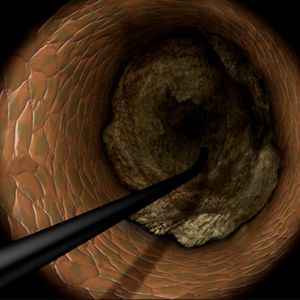

Join us for a live-streamed workshop where the world's top cardiologists gather to explore cutting-edge techniques in PCI (Percutaneous Coronary Intervention), with a special focus on the advanced Tip Detection Antegrade Dissection Re-entry (TD-ADR) method.

- Innovative Techniques: Master the latest technologies, including the highly-regarded 3D wiring technique and TD-ADR, developed in Japan, and stay at the forefront of medical innovation.